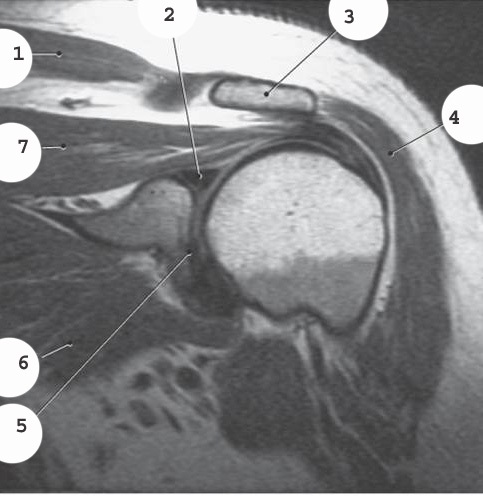

acromion

labrum

4

deltoid

5

glenoid

7

supraspinatis muscle